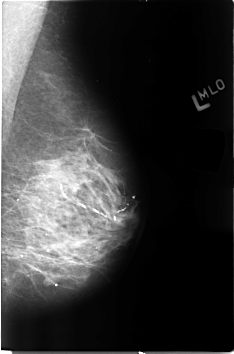

B_3129_1.LEFT_MLO

LEFT_MLO LINES 4592 PIXELS_PER_LINE 3032 BITS_PER_PIXEL 12 RESOLUTION 50 NON_OVERLAY

DATE_OF_STUDY 27 2 1997

PATIENT_AGE 71

DENSITY 3